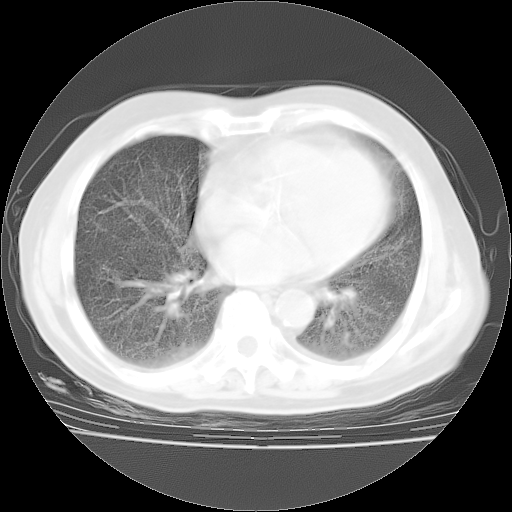

4月14日肺部CT

楼主| 发表于 2010-4-28 16:51 | 显示全部楼层

楼主| 发表于 2010-4-28 16:53 | 显示全部楼层

肺部CT平扫未见异常。